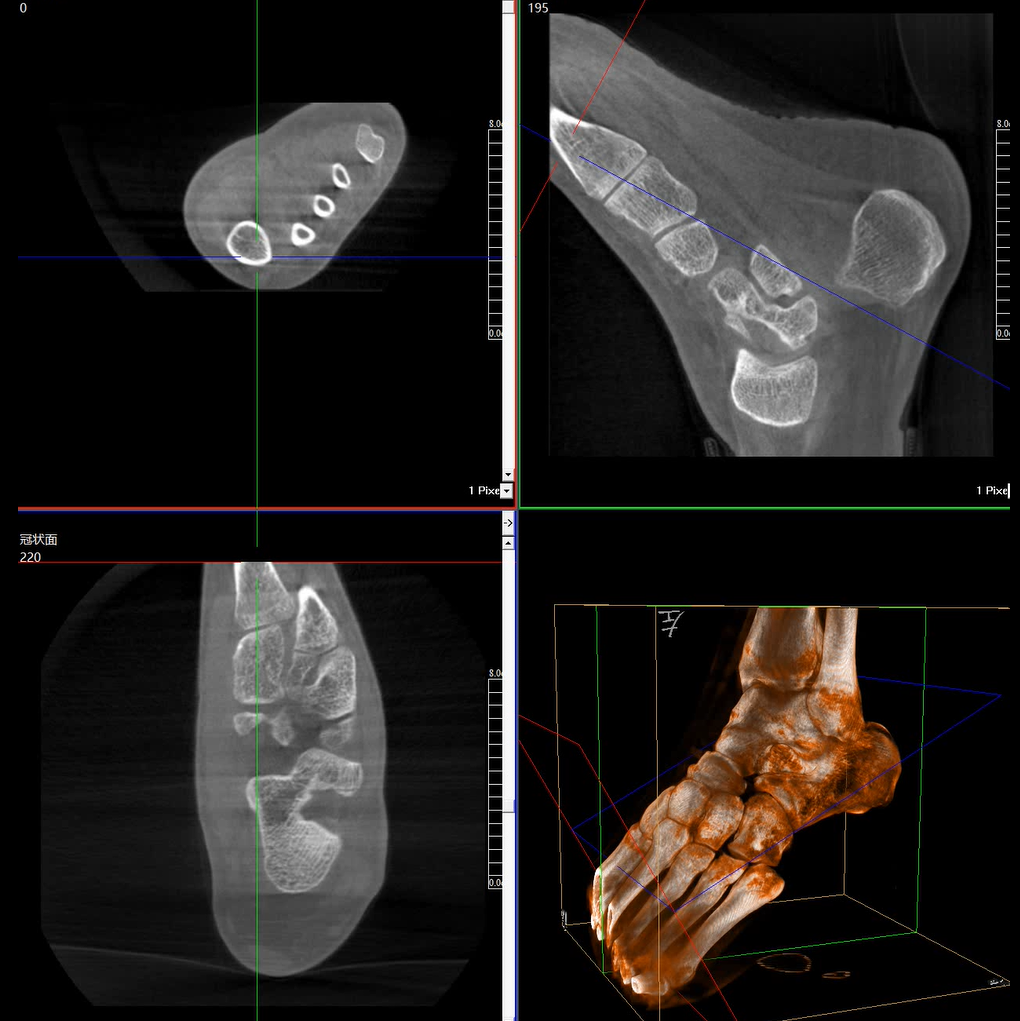

術(shù)中三維成像和橫斷面圖像提供多角度的手術(shù)診斷信息,輔助醫(yī)生進(jìn)行術(shù)中評(píng)估判斷,諸如骨折復(fù)位情況和內(nèi)植入螺釘?shù)某叽绾臀恢茫o助手術(shù)更好地完成。

提供更大的術(shù)中三維成像視野,采集更多圖像信息,可一次拍全全段頸椎、全段腰椎、七節(jié)胸椎、雙側(cè)骶髂關(guān)節(jié)、股骨頭及單側(cè)盆骨。

平板垂直升降運(yùn)動(dòng) 便于術(shù)中微調(diào)平板與拍攝主體的距離,更加貼近病灶體,成像范圍更大,圖像更清晰。